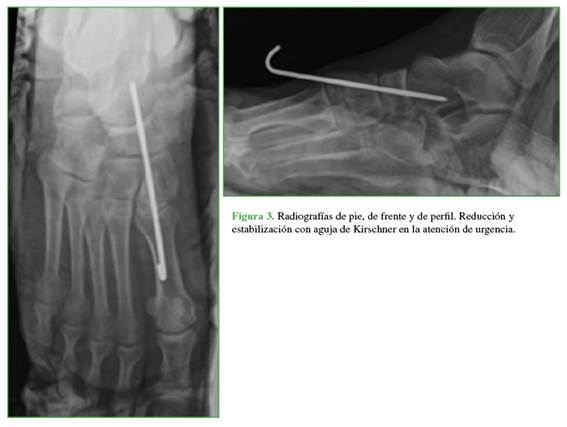

A las tres horas de la admisión y luego de realizar los estudios complementarios correspondientes, el paciente fue trasladado al quirófano donde se le practicaron maniobras de reducción cerrada y estabilización por medio de una clavija de Kirschner tomando primera cuña, navicular y cuboides. Todos los procedimientos se realizaron con asistencia radioscópica. Se lo inmovilizó con una férula suropédica y se tomaron radiografías posoperatorias, en las que se comprobó una reducción articular aceptable y se programó la fijación definitiva diferida (Figura 3).